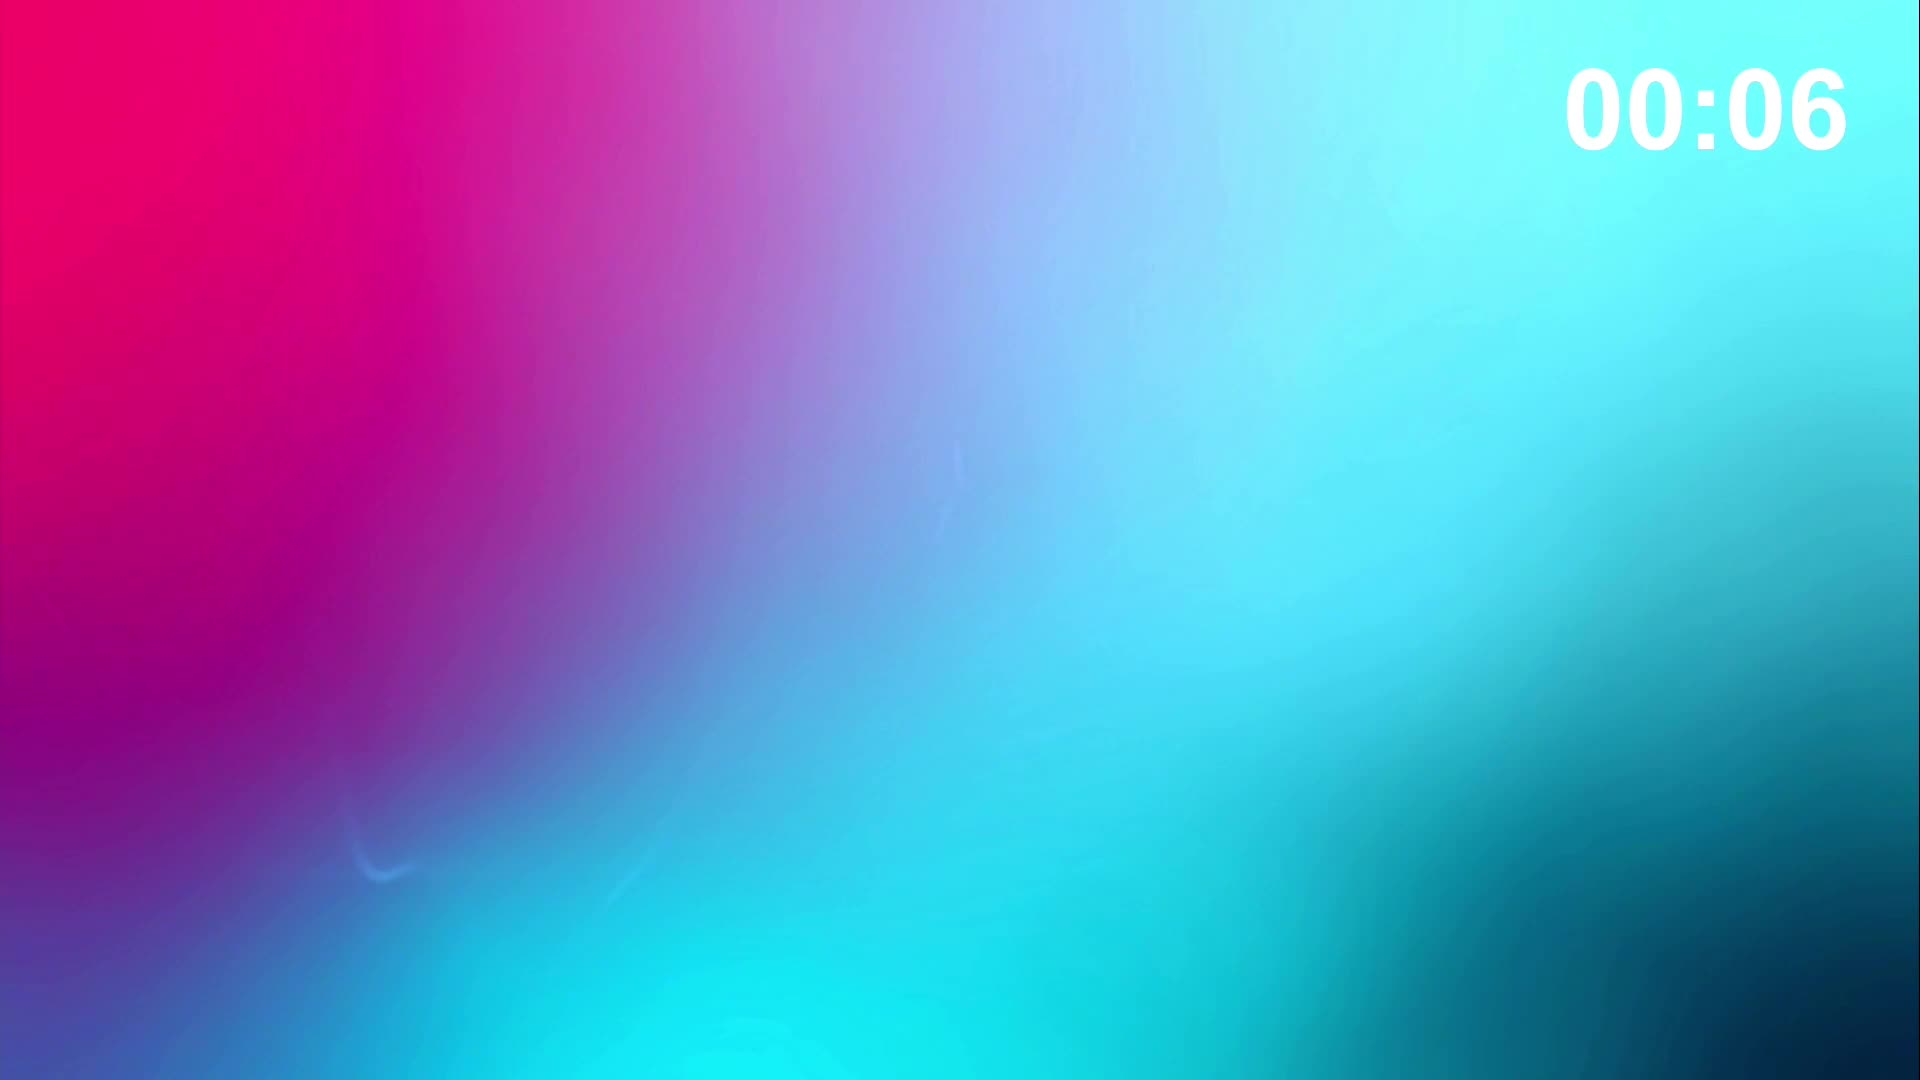

Session 1: Pre-procedure planning – are we lost without a map?